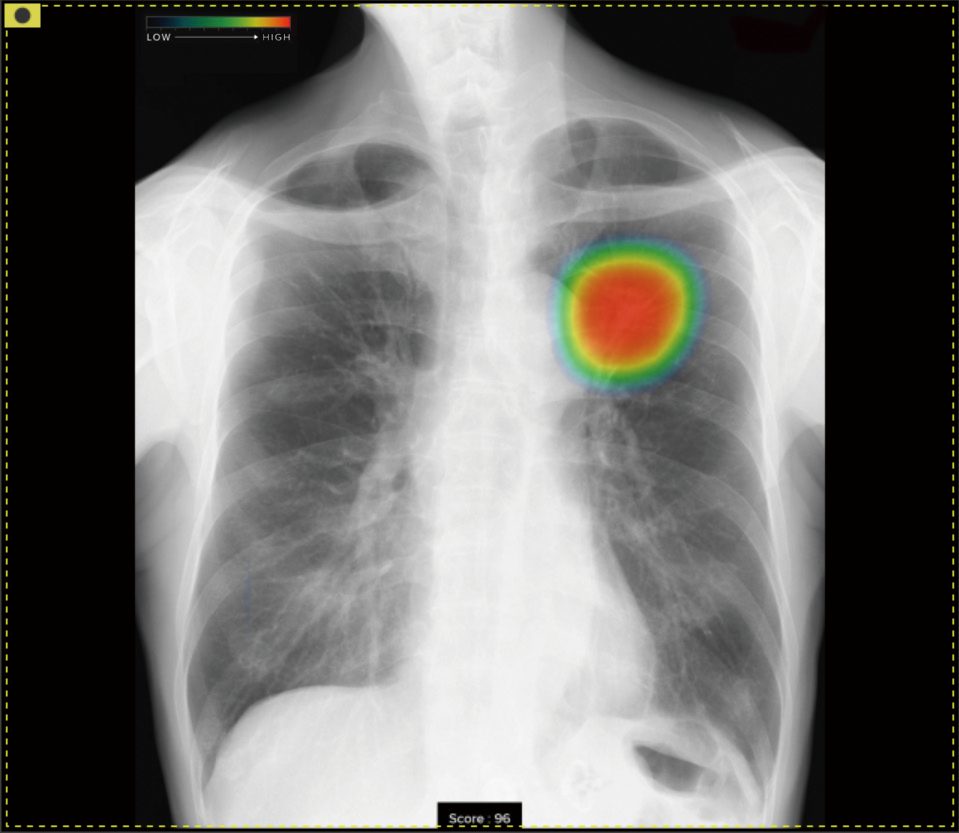

■一般撮影システム CLINIX Plus / CALNEO Flow

• 当院では、富士フイルム製の一般撮影システムを導入しております。

• 高感度な富士フイルム製のFPDを組み合わせているため、高画質を実現しております。

• 小型拡張ユニット(EX-mobile)も付属し、内蔵の胸部X線画像病変検出ソフトウェアによって、医師の画像診断をサポートします。